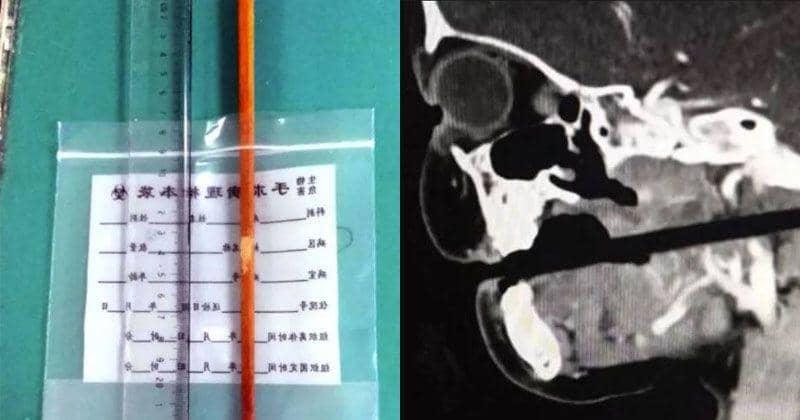

Malang, ia pun terjatuh dan kemudian sumpit yang dipegang tersebut menembus ke sisi mulutnya hingga menembus tengkorak.

Rupanya, sumpit tersebut telah masuk begitu dalam sampai ujung sumpit dapat dirasakan dari belakang lehernya.

Setelah dilakukan CT scan, dokter mengungkapkan bahwa sumpit tersebut nyaris meleset menusuk bagian vital seperti batang otak, arteri karotid, dan vertebra leher. Bahkan sekitar 10 cm, sumpit tersebut telah masuk ke kepalanya.

Setelah dilakukan operasi, akhirnya sumpit pun berhasil dilepas, dan anak tersebut kini berada dalam kondisi stabil, meski masih tetap diamati.